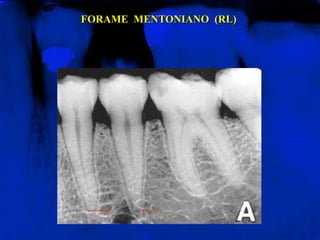

FORAME  MENTONIANO  (RL)Área radiolúcida arredondada ou oval, de pequena extensão, localizado, na maioria dos casos, entre os ápices dos dois pré-molares

FORAME  MENTONIANO  (RL)